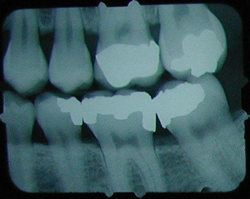

No cavity on first X-ray.

Months later, cavities that start between the teeth can't be seen by visual examination, but they can be detected on an X-ray.

This cavity was detected and filled before the patient felt any discomfort, and before the nerve became infected or the tooth became abscessed.

There is another cavity shown in the X-ray on the right. Can you find it? It's difficult for the untrained eye to spot. Click here to see where it is. (Hint: It's not the left edge of the top left tooth. That's just the edge of the frame around the X-ray).